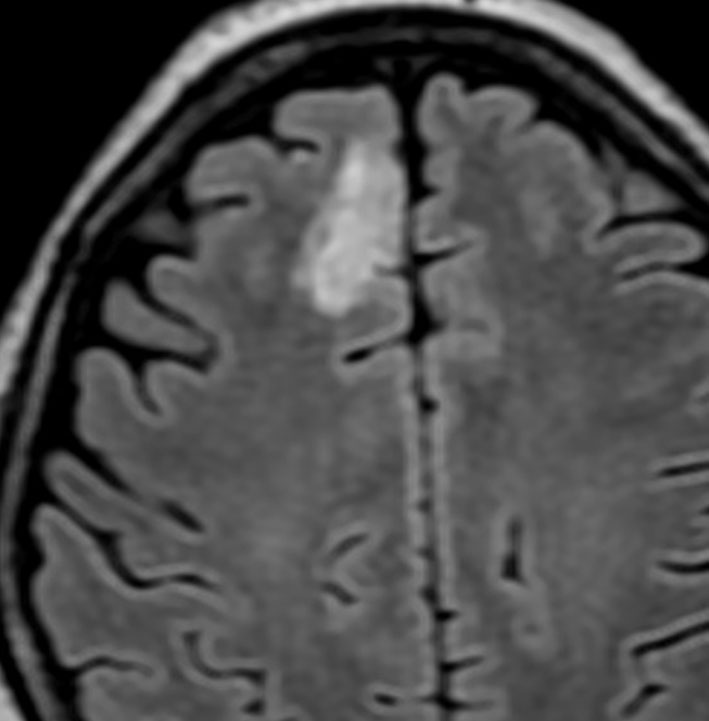

• MRI-T1強調画像では低信号となり,T2強調画像とフレア画像では高信号域となります

• グリオーマの中では,T2強調画像での腫瘍内部のコントラストが強く,石灰化の部分は強い低信号域として,のう胞は均一な強い高信号域となります

• 周囲脳組織浮腫あるいは腫瘍浸潤部は淡い高信号域として描出されます

• 脳浮腫を伴うものはグレード3の可能性が高いです

• ガドリニウムによる造影では,悪性度が高くなるにつれて部分的な増強像が増えます

MRI画像ではびまん性星細胞腫と区別がつかないものがあります